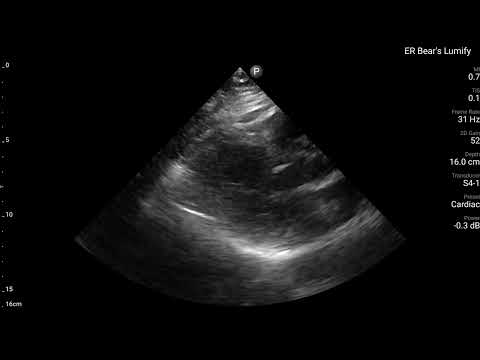

當下有幫病患做echo,讓我們來看看echo有哪些findings?

藉由echo,我們可以看到,LAD支配的Ant.wall幾乎不太動。(請搭配Fig.4安心服用)

ECG在LAD支配位置的Precordial leads出現Subtle STE/PRWP/HATW/此外10分鐘後的dynamic STTC,另外加上echo看到ant.wall有RWMA。這些證據不管怎麼樣都實實在在說明,LAD出現問題了。